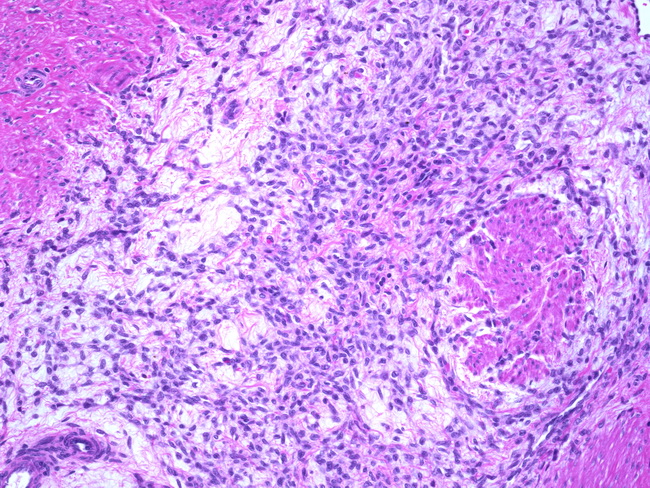

Myxoid Leiomyosarcoma. A, The Tumor Has An Infiltrative Growth Pattern

www.researchgate.net

www.researchgate.net

leiomyosarcoma myxoid tumor infiltrative growth leiomyoma necrosis tumors myometrium hypocellular abundant uterus eosin minimal atypia hematoxylin magnifications

leiomyosarcoma uterus myxoid pathology webpathology comments

Webpathology.com: A Collection Of Surgical Pathology Images

www.webpathology.com

www.webpathology.com

leiomyosarcoma uterus myxoid pathology webpathology stroma comments

Figure 1 From Myxoid Leiomyosarcoma Of The Uterus. | Semantic Scholar

www.semanticscholar.org

www.semanticscholar.org

uterus leiomyosarcoma myxoid